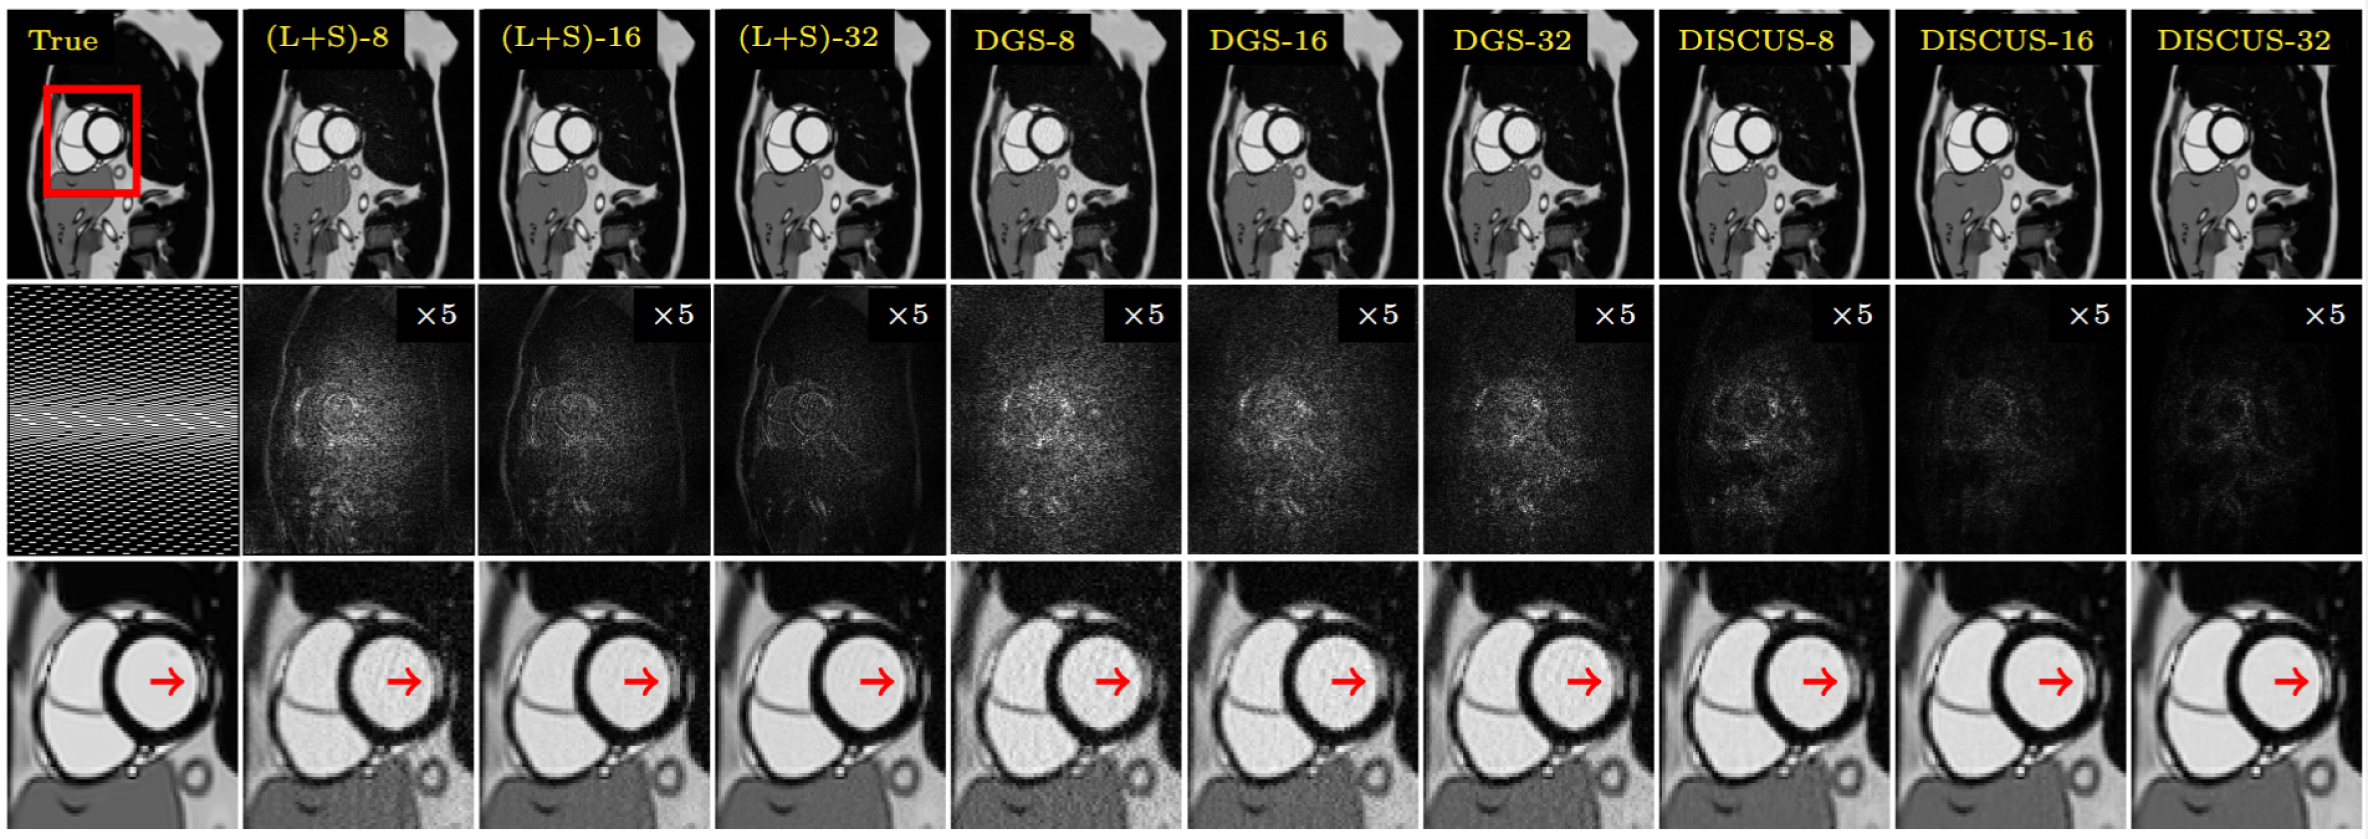

Refer to caption

Figure 4: Representative results from the ablation study of the simulated LGE (Study II) exhibiting a pronounced myocardial scar at R=4𝑅4R=4italic_R = 4. First row shows an example frame with reference (left) and reconstructions by L+S, DGS, and DISCUS with 8, 16, and 32 frames. Second row contains the GRO sampling pattern (left) where frames are displayed left-to-right, phase encoding is shown top-to-bottom, and frequency encoding is omitted, and ×5absent5\times 5× 5 error maps. The final row provides a zoomed-in view of the red box in first row, with the red arrows pointing to the scar.

The findings of the ablation study, where we investigate the impact of T𝑇Titalic_T and the group sparsity, are summarized in Table 3. In this study, we only compare methods that jointly recover all the frames, i.e., L+S, DISCUS, and DISCUS without group sparsity (DGS). As expected, the performances of all three methods degrade with a decrease in T𝑇Titalic_T, indicating that these methods exploit the joint information across the frames. Also, across all three values of T𝑇Titalic_T, DISCUS maintains an advantage of more than 3 dB over DGS. Since DGS is identical to DISCUS except for the group sparsity, these numbers highlight the impact of manifold learning in DISCUS. The dimensionality of the manifold discovered by DISCUS was either one or two across all six simulated LGE images. Forcing the manifold dimensionailty to one resulted in degradation of reconstruction quality. A representative image from the ablation study is shown in Figure 4. Both DGS and L+S exhibit noise amplification, especially at T=8𝑇8T=8italic_T = 8.